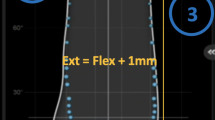

3D reconstructed patient femora and tibiae were generated using the imaging software ScanIP (Simpleware, Exeter UK) from pre-operative CT scans [6]. Landmarks describing bone and soft-tissue references are identified by trained engineers qualified by the lead study author used to define patient-specific bone axes and soft-tissue attachment sites [22, 26]. The pre-operative models and landmarks were registered to the post-operative CT scan. In addition, 3D implant models of the implanted components were also registered to the post-operative CT scan. This whole process has been previously shown in a validation study to produce maximum errors of 0.9° ± 0.6° and 0.5 mm ± 0.3 mm with an intra-class correlation coefficient (ICC) > 0.93 indicating excellent reliability [28]. These models, landmarks and component positions were used to produce a computational simulation (see Fig. 1). The simulation replicates a deep knee bend performed in an Oxford Knee Rig (OKR), and includes modelled collateral ligaments, a quadriceps tendon and other passive soft-tissue restraints. All ligaments were modelled as one or two bundles of nonlinear springs as described by Abdul-Rahman et al. [1] with fixed parameters further adapted using a process previously described by Theodore et al. [22, 23, 26]. In this way, the model captures the combination of patient-specific elements, component geometry and component position and orientation that contribute to the dynamic joint motion.

The alternate simulation sets used to cover other surgical plans covered (a) altered posterior resections (+3 mm to – 3 mm resection in 1mm increments), (b) altered tibial slopes (0–12 degrees in 3-degree increments) and (c) altered femoral rotation (matched to the Posterior Condylar Axis (PCA) or matched to the surgical Transepiconylar Axis (TEA)). This gives a total of 13 simulations per patient, which combined with their simulation of actual surgically achieved position amounts to 14 simulations per patient. Evaluation questions were compiled from the KOOS questionnaire to investigate for a relationship to the specific simulated kinematic response expected from the investigated component alignment change. For slope and posterior resection, the following three questions relating to Range of Motion (ROM) were evaluated: “Can you straighten your knee fully?”, “Can you bend your knee fully?”, “Do you experience difficulty descending stairs?”. For femoral rotation, responses to three questions focused on patellar function were evaluated: “Does your knee catch or hang up when moving?”, “Do you feel grinding, hear click or any other type of noise when your knee moves?” and “Do you experience difficulty squatting?”.